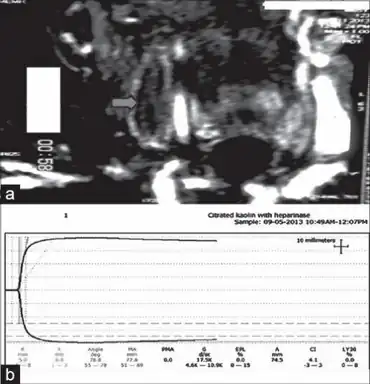

a) Image depicting thrombus in right internal jugular vein b) thromboelastogram showing hypercoagulability

Tests for thrombophilia include complete blood count (with examination of the blood film), prothrombin time, partial thromboplastin time, thrombodynamics test, thrombin time and reptilase time, lupus anticoagulant, anti-cardiolipin antibody, anti-β2 glycoprotein 1 antibody, activated protein C resistance, fibrinogen tests, factor V Leiden and prothrombin mutation, and basal homocysteine levels.[2] Testing may be more or less extensive depending on clinical judgement and abnormalities detected on initial evaluation.[2]

Recurrent miscarriage is an indication for thrombophilia screening, particularly antiphospholipid antibodies (anti-cardiolipin IgG and IgM, as well as lupus anticoagulant), factor V Leiden and prothrombin mutation, activated protein C resistance and a general assessment of coagulation through an investigation known as thromboelastography.[10]